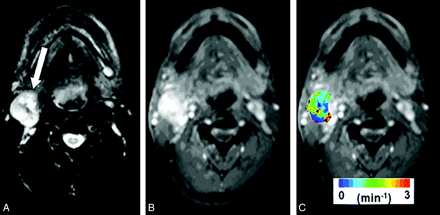

Median pretreatment Ktrans values were computed from the largest metastatic nodal mass by using only the central 4 sections to avoid erroneous results from wrap-around artifacts, typically observed on the end sections of the 3D images. Representative pretreatment structural MR images and a color-coded pharmacokinetic parametric Ktrans map, overlaid on a postcontrast T1-weighted image from a patient, are shown in Fig 1.

Representative images from a patient with HNSCC before chemoradiation therapy. A, Axial T2-weighted image demonstrates a heterogeneous hyperintense metastatic lymph node at level IIa of the right neck (arrow). B, This mass exhibits heterogeneous enhancement on a contrast-enhanced T1-weighted image. C, DCE-MRI−derived Ktrans map is shown as a color image overlaid on a postcontrast T1-weighted image.